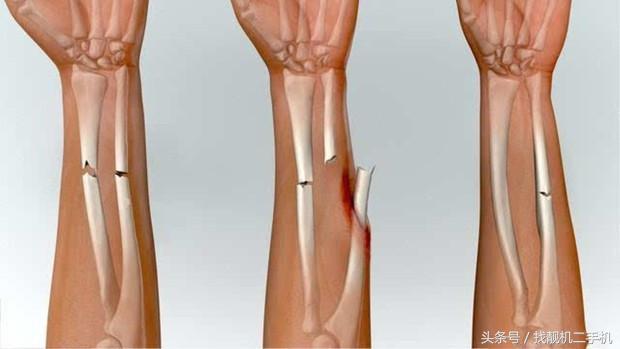

一般来说,骨折治疗主要分为以下复位、固定、功能锻炼三个步骤。 其中复位分为闭合复位和手术复位。如果是脱臼,或者轻微性骨折, 那么就可以在不损伤皮肤的情况下,用手或者用仪器将骨头恢复原位,再加以石膏固定,等骨头自己慢慢长合。

如果情况不幸,遭遇了重创,骨头碎裂比较严重, 那就得靠手术复位了。手术时,医生会将切开患处皮肤,用钢丝缝合,再根据情况选用螺丝钉、钢板、三刃钉、髓内针等内固定骨头。

更严重的,还需要将碎骨取出,用其他部位的骨头植入缺损处,最后加上石膏外固定。不过,尽管有双重保障,但粉碎性骨折一般很难恢复到原貌。